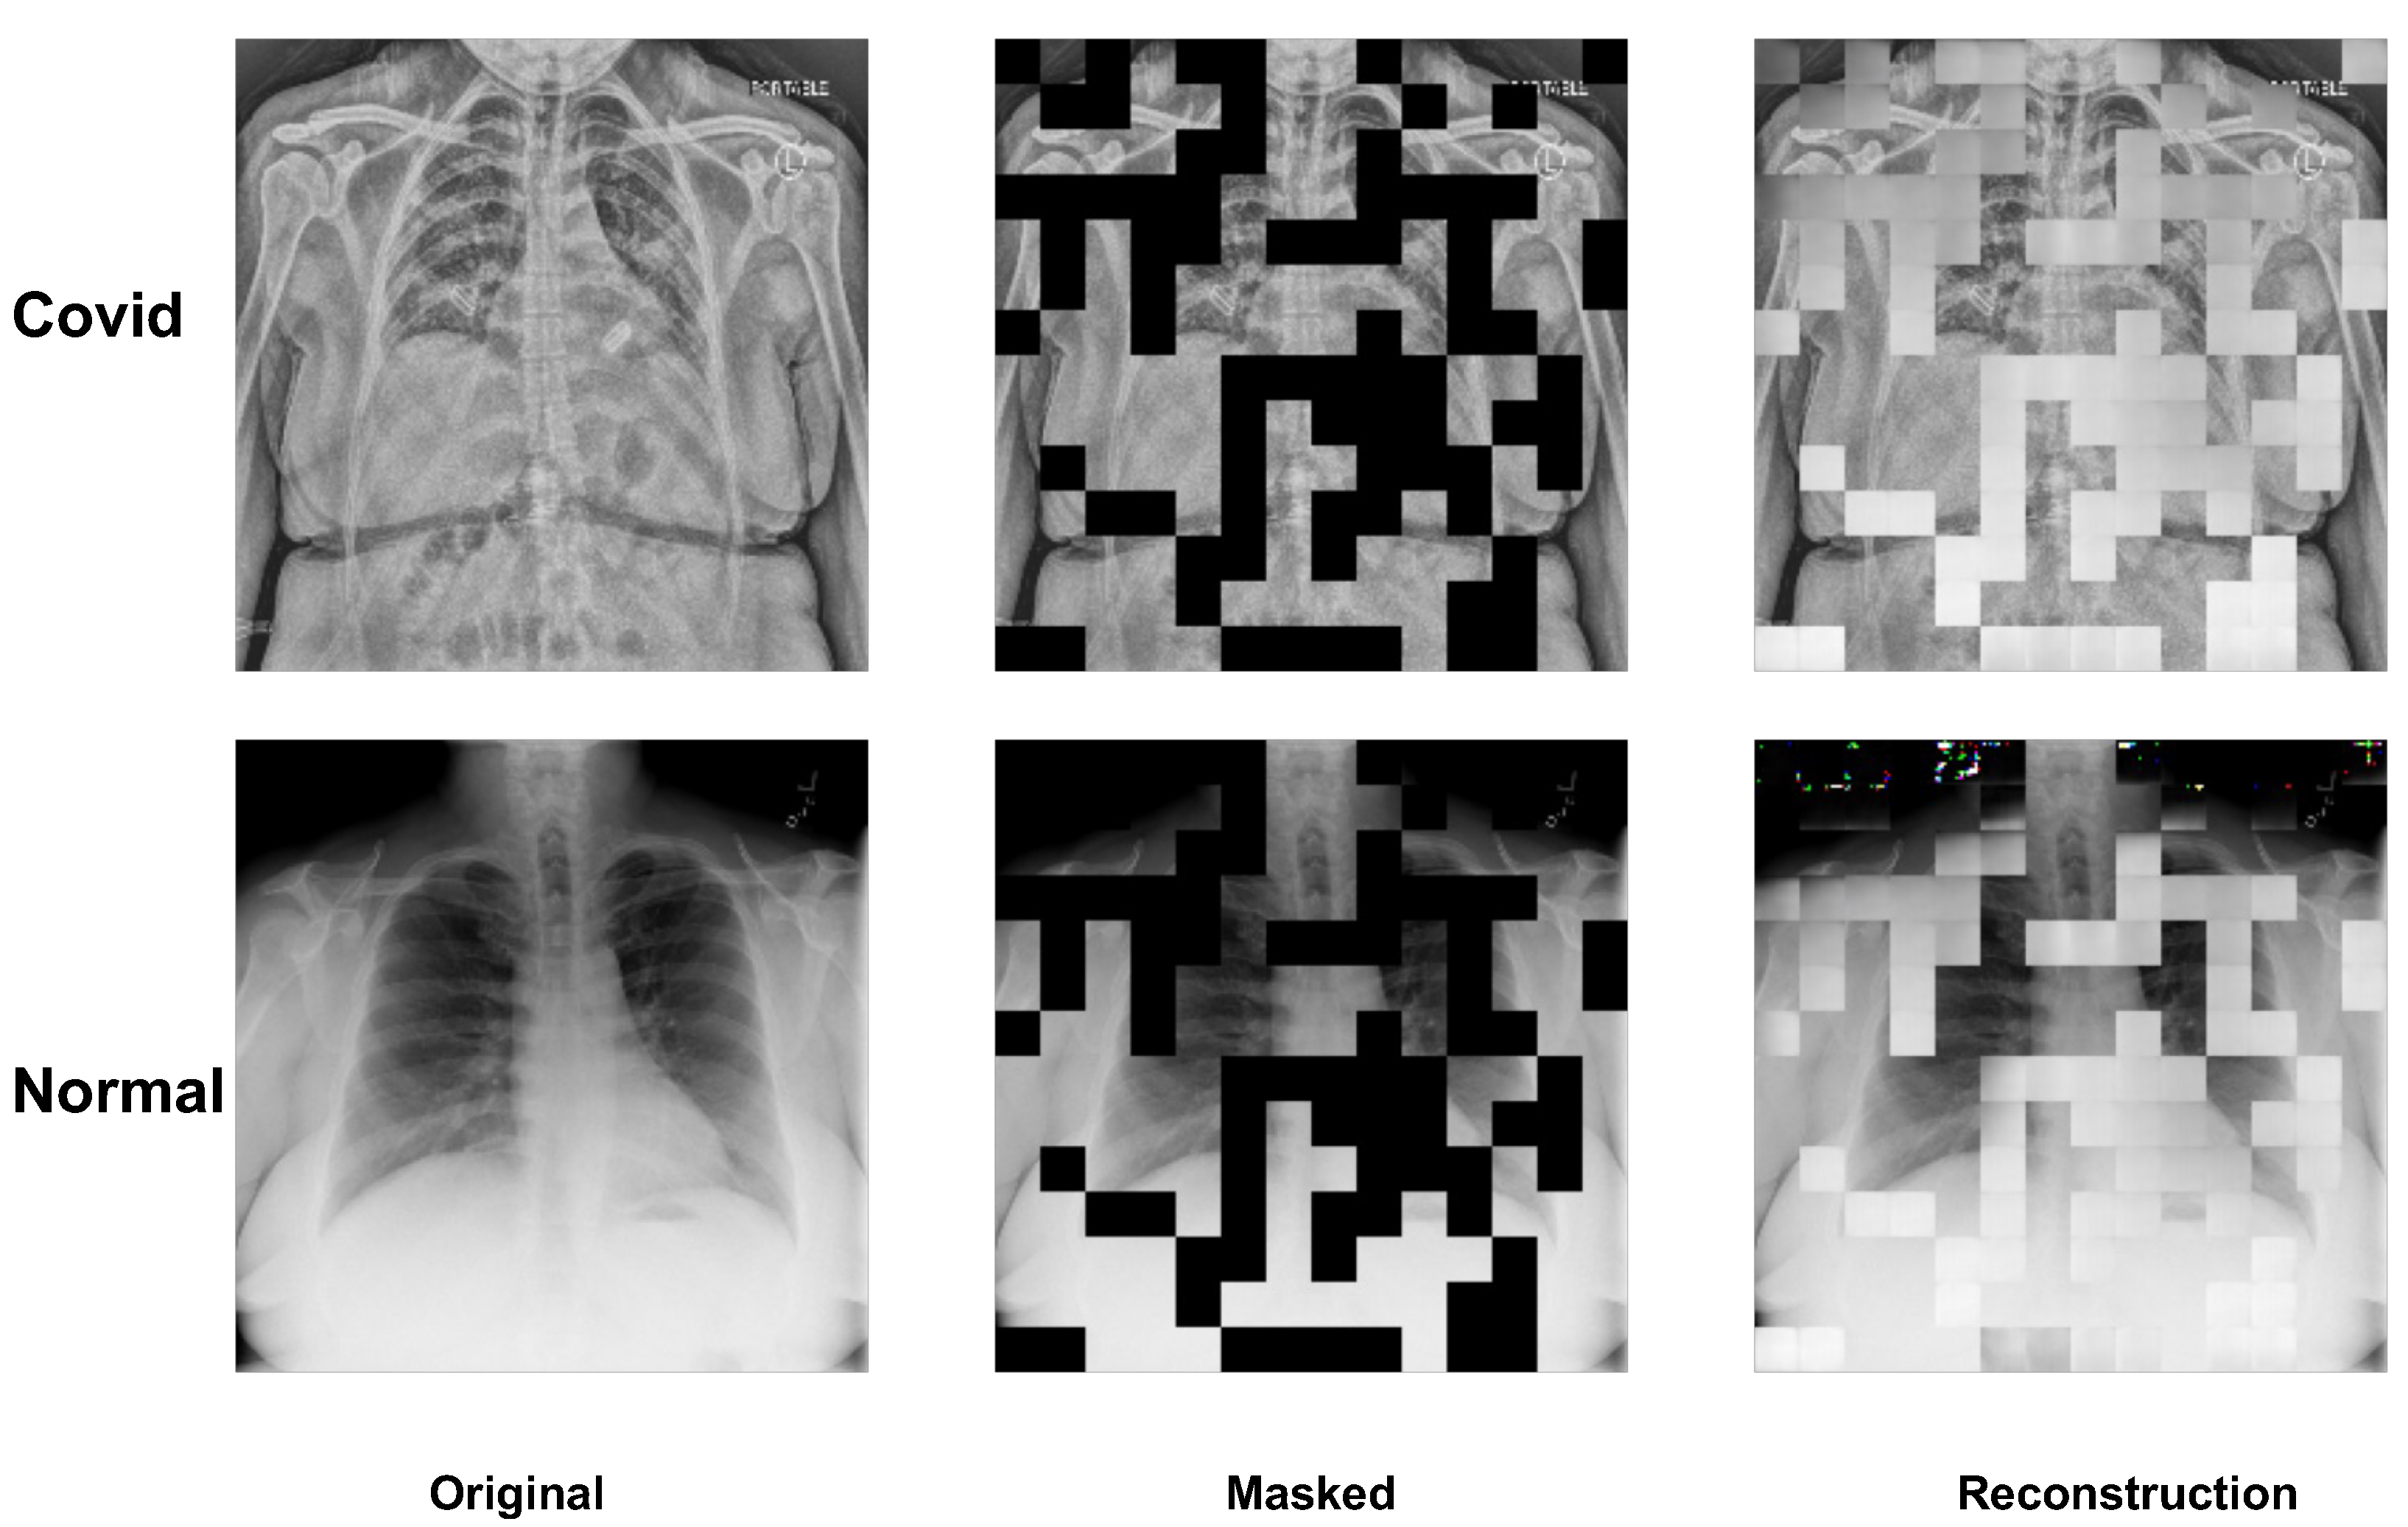

3.4. Visualization of MAE on Image Reconstruction